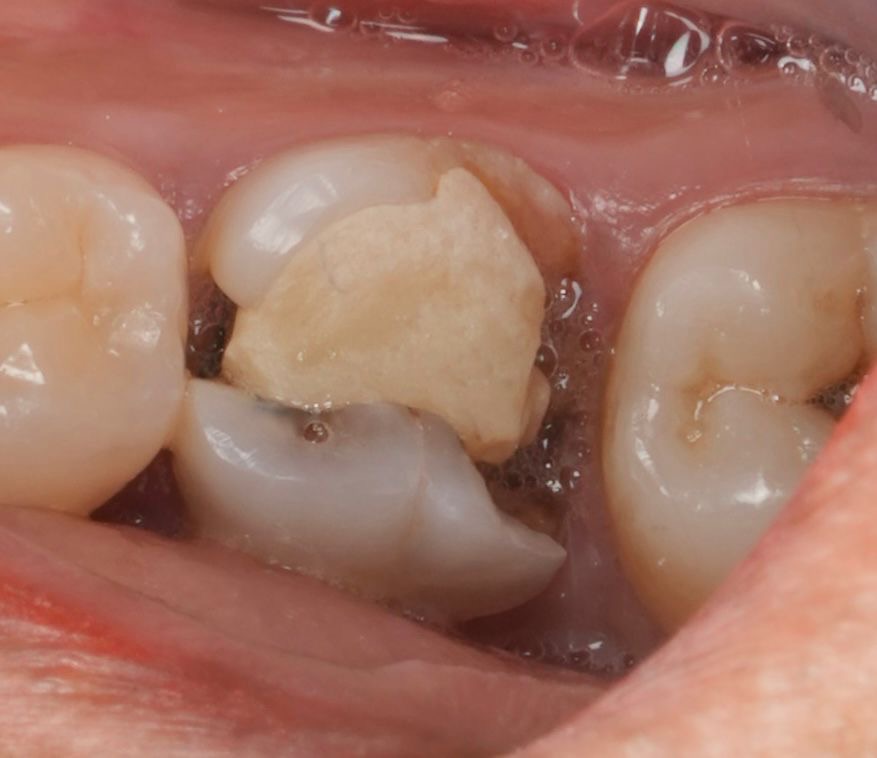

Definitive Restoration

- Core build-up completed using dual-cure composite core material.

- Tooth prepared conservatively for full coverage.

- Definitive crown fabricated in monolithic zirconia for strength and longevity.

- Bonded with resin cement under isolation.

- Occlusion refined to preserve functional harmony.